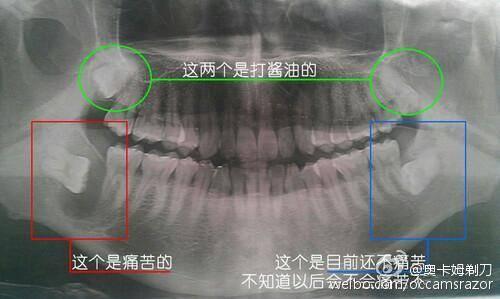

如果想要判断自己是不是阻生智齿,去牙科医院诊所拍个牙片就可以了。基本上片子在手的时候,就很容易心里有数了,因为斜着横着长都很容易看出来…当然,一定要遵医嘱行事。